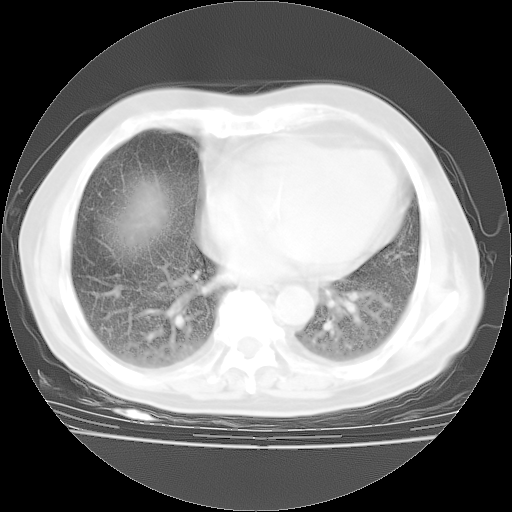

4月28日肺部CT——再次出现类似去年5月9日——磨玻璃样、间有“粟粒样”改变。

4月28日肺部CT——再次出现类似去年5月9日——透光度降低,“间质性”改变。

个人阅读4.14日肺部CT平扫:纵隔窗无异常,但肺窗示:双下肺内、后基底段有片絮状侵润影,部位以后基底段为著,以间质改变为主,呈急性肺泡炎征像,和首次住院影像学有相似之处。仅是个人读片,明日请相关专家再读片哈。其它建议同上。